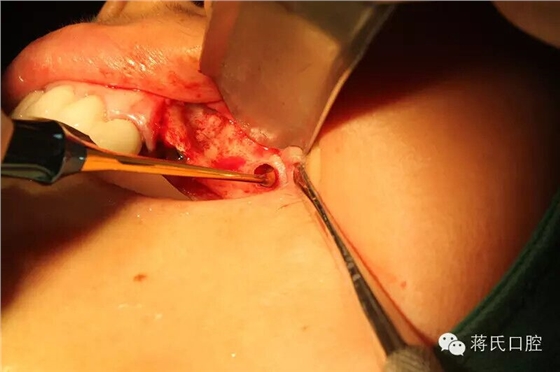

10.左側(cè)切開后

11.第一洞制備完成

12.左側(cè)外提升過程